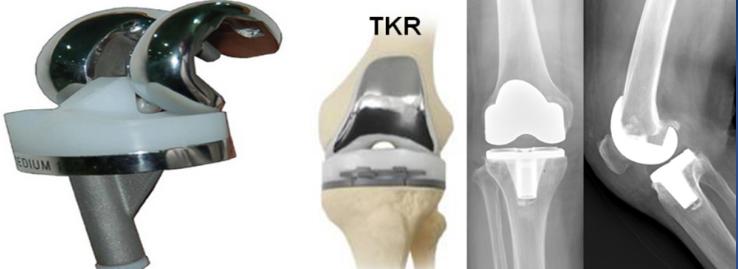

a.全膝关节表面置换(TKR):主要用于累及范围比较广泛的膝关节骨性关节炎患者。

5)膝关节置换术后康复:膝关节置换术后一般在麻醉过后即可开始功能锻炼,在术后次日即可以下床行走,术后3个月恢复日常生活和工作,人工关节完全达到最佳使用状态大约6个月至1年。

6)人工膝关节置换术后使用年限:大于90%的人可以使用超过20年。